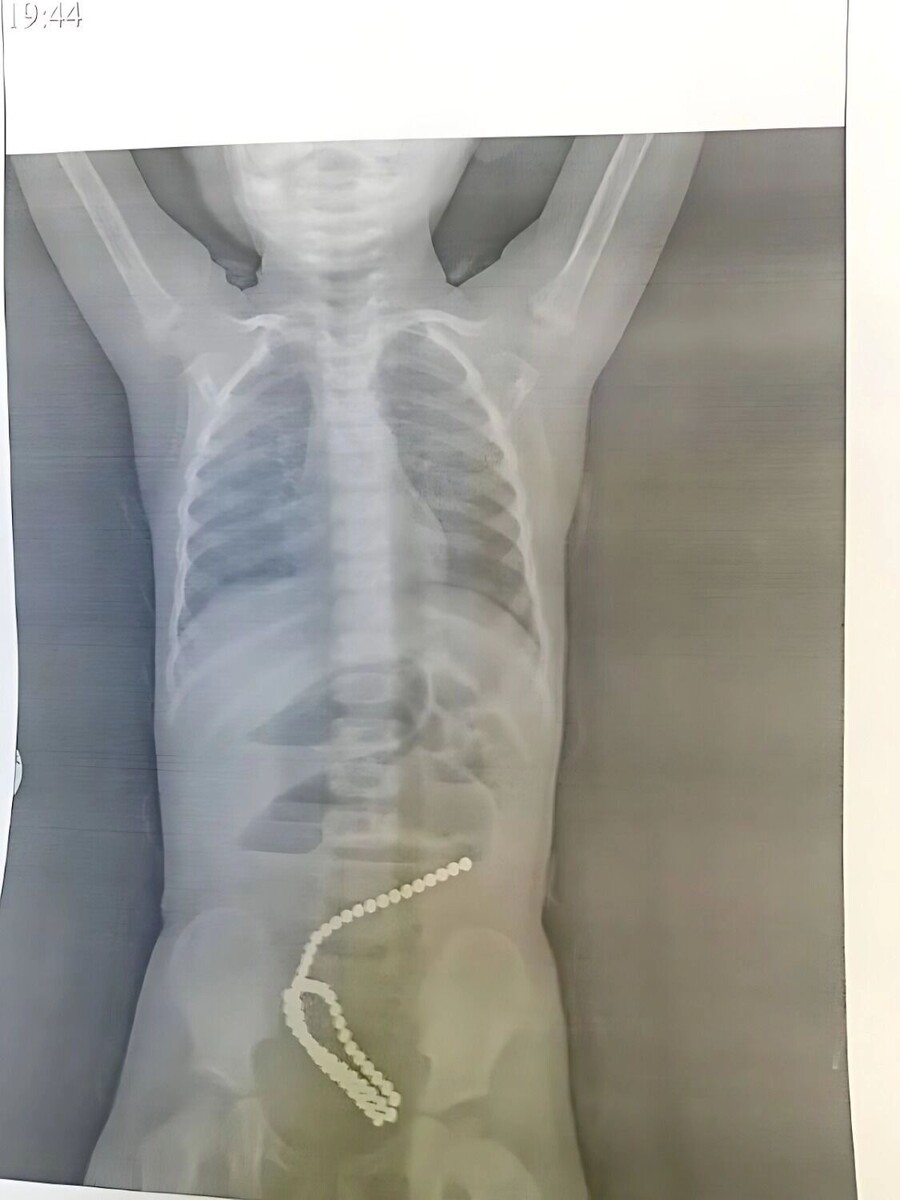

Опасные магниты в кишечнике: девочку из Комсомольска-на-Амуре пришлось спасать

Сделав рентгенологическое исследование, врачи сразу поняли причину болей. В кишечнике девочки находились магниты — шесть десятков маленьких, собранных в единую цепь шариков. Такие магниты продают как развивающую игрушку, но в кишечние они представляют серьёзную угрозу здоровью.

Сами по себе шарики гладкие и вряд ли травмируют кишечник. Однако, в процессе прохождения по тракту, они могут смыкаться и критически сдавливать кишечную стенку. Ткани могут омертветь, что переведёт к перфорации кишечной стенки, вероятна закупорка кишечника. У пациентки магниты повредили стенок и вызвали кишечную непроходимость.

Потребовалось хирургическое вмешательство, которое специалисты провели с успехом. Девочка поправляется.